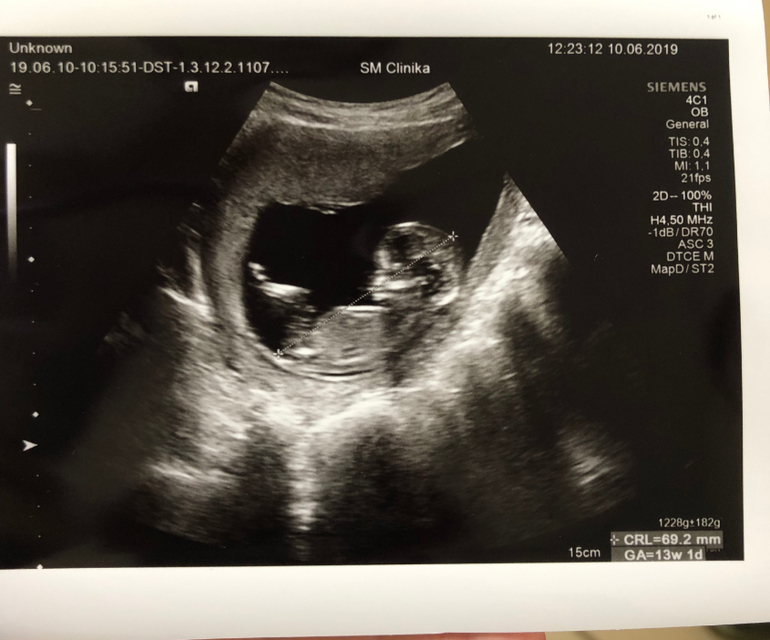

По УЗИ

КТР = 74,8 мм

Шейная складка - 1,70 мм